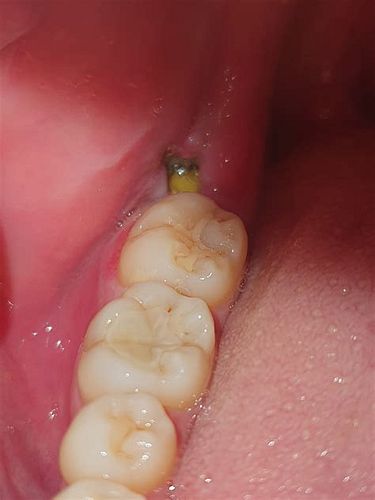

사랑니 통증은 보통 사랑니가 나는 과정에서 잇몸이 부풀거나 염증이 생기면서 발생합니다. 또한 사랑니 주변에 음식물이 끼어 세균 감염이 쉽게 일어나 통증과 붓기, 입 냄새 등 여러 증상을 유발할 수 있습니다. 매복된 사랑니나 기울어져 난 사랑니는 잇몸 염증과 앞 어금니 충치를 유발할 가능성이 높아 통증이 더 심해질 수 있습니다.

매복된 사랑니가 앞으로 기울어 있으면, 앞 어금니 뒤쪽 면에 음식물이 쉽게 끼어 충치(치아우식증)가 발생하기 쉽습니다. 이 충치가 진행되면 통증이 나타나고, 충치가 심해지면 앞 어금니의 신경 손상과 통증, 심한 경우에는 앞 어금니의 상실로 이어질 수 있습니다. 또한 매복 사랑니가 주변 잇몸과 뼈에 염증을 유발하면, 앞 어금니 주위의 골 손실과 잇몸 손상도 발생해 치아 지지력이 약해질 수 있습니다.